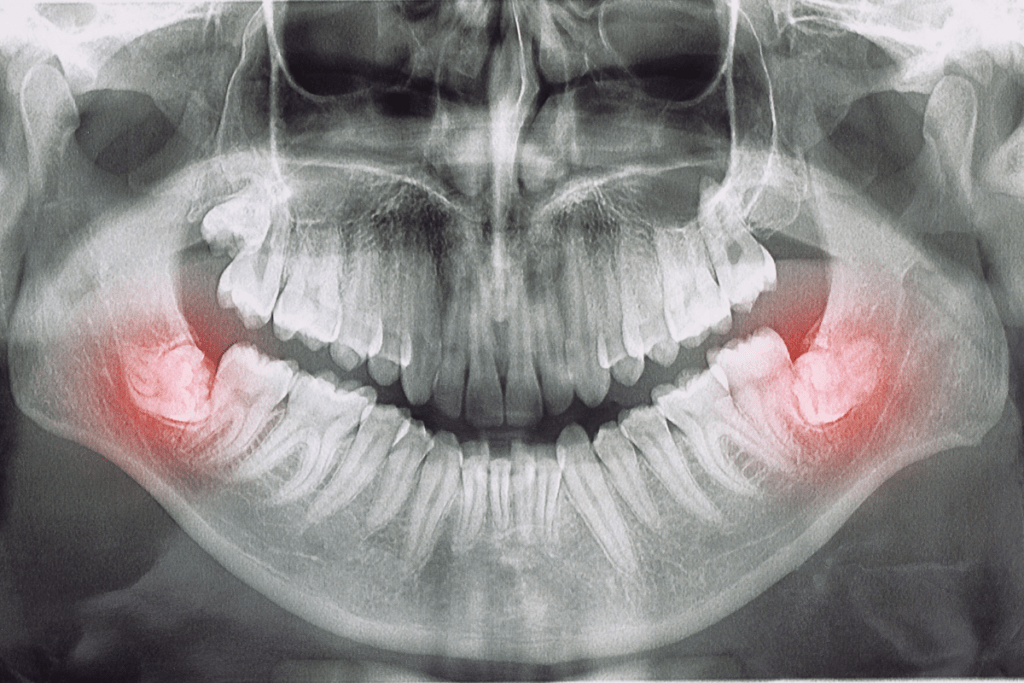

Originariamente son cuatro. Dos aparecen en la parte de atrás del maxilar superior (una a cada lado) y las otras dos en el maxilar inferior. Aunque no siempre erupcionan todas. Cuando no tienen espacio suficiente en la arcada dental pueden quedarse retenidas.

• Infecciones y enfermedad periodontal: La pericoronaritis es una inflamación infecciosa bastante frecuente durante la aparición de las muelas del juicio.

• Apiñamiento: Se produce cuando las cordales no tienen espacio para salir o están mal posicionadas y empujan otros dientes definitivos moviéndolos.

• Quistes: Pueden formarse bajo la muela y dañar la mandíbula y los nervios.